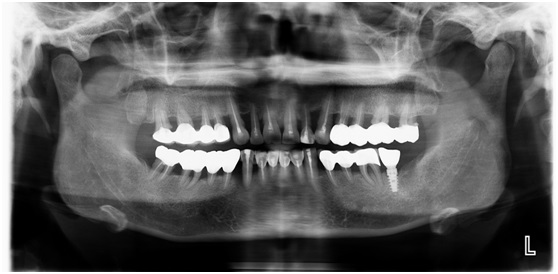

X线检查

牙周疾病比较复杂,需要一段治疗周期。先进行口内洁治和药物治疗,然后再行

全口牙齿的根管治疗。